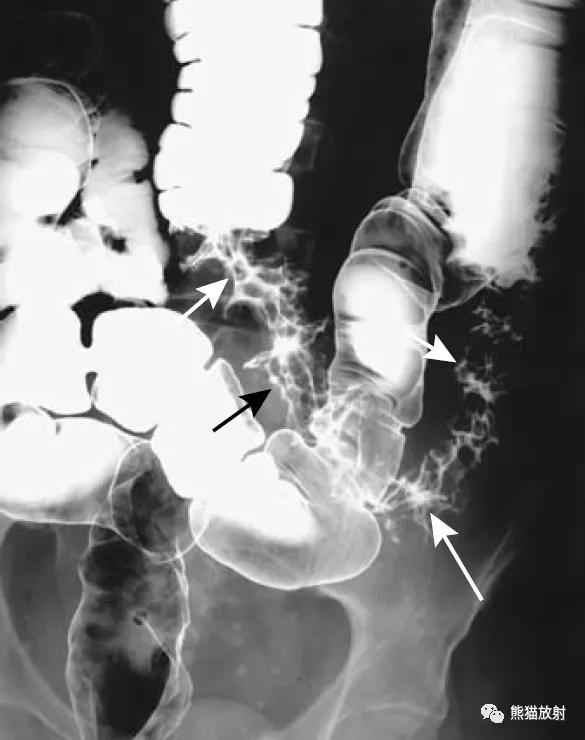

克罗恩病(Crohn's disease)。存在广泛的丝状息肉。